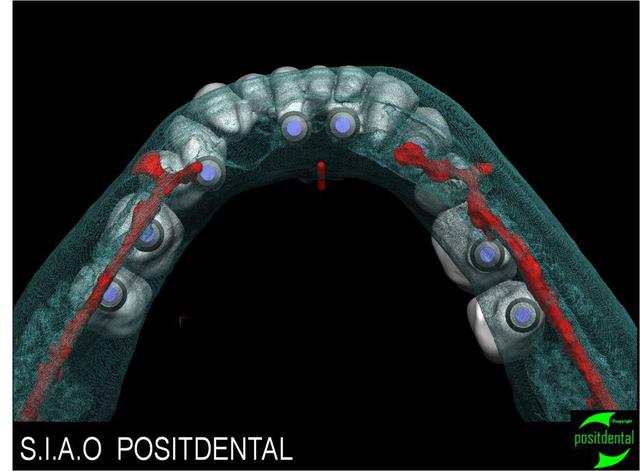

Etude en vue d'une extraction implantation pour la réalisation d'un bridge transvissé sur implants master-L.

Extraction virtuelle du bridge et des racines.

Reconstitution du projet prothétique à partir du volume de l'ancienne prothèse et de l'adjonction de 37/36/46/47

Vue d'ensemble du projet prothétique et implantaire.

rapport entre les implants, le N.A.I et l'artère sublinguale.